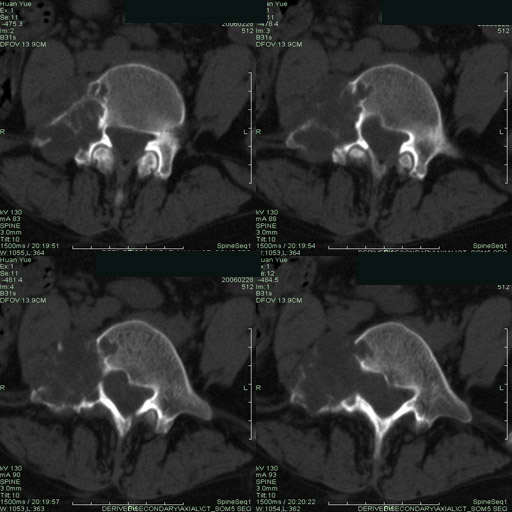

以下是引用听蝉观竹在2006-3-5 23:09:00的发言:[br]这个病例不考虑神经源性肿瘤,首先考虑转移瘤,因为它不是受压造成骨质吸收,而是从骨骼的松质部分由中心向外破坏的,不仅仅是横突,而且同侧椎弓根也破坏了。[br]神经源性肿瘤-----受压造成骨质吸收。[br]转移性肿瘤------从骨骼的松质部分由中心向外溶骨破坏,多见椎弓根也破坏。

以下是引用徐大夫在2006-3-5 20:32:00的发言:[br]骨缺损区边缘有硬化,结合部位,考虑神经源性良性肿瘤。